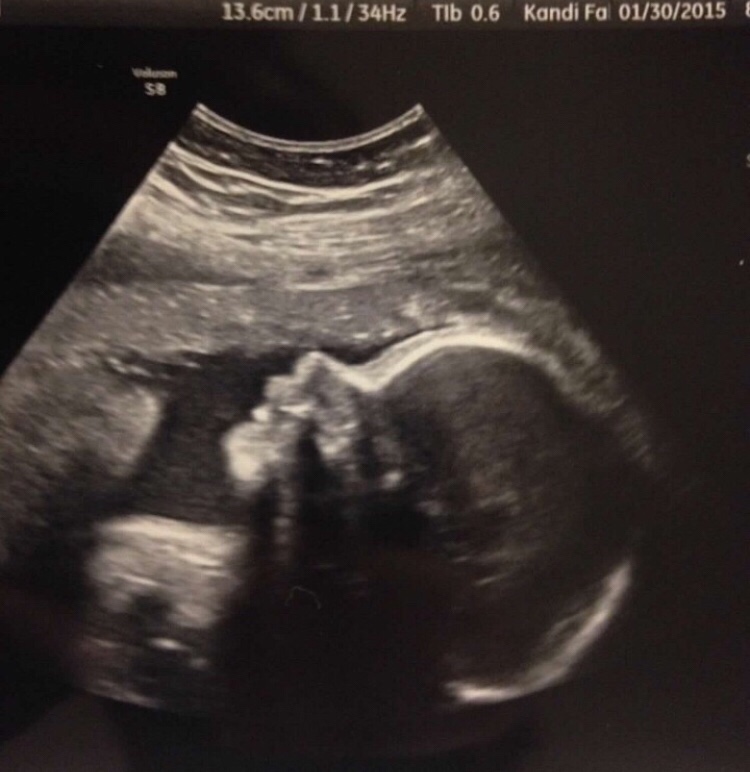

We were lucky enough to see her a few times on ultrasound! The first time when she looked like a frog (seen in the previous blog), another time when she looked like a gummy bear (also seen in the previous blog), then again around 15 weeks to find out that she was a girl, again at 20 weeks for an anatomy scan, 24 weeks for an additional look at her heart, and one more at 28 weeks to prepare for us flying to Puerto Rico! We loved seeing her so much!!

The ultrasound sound girl placed the monitor on my belly, and I immediately saw her heart. Since I know what I’m looking at, she didn’t have to speak. I could see everything and in the same instance I saw nothing. Nothing moving. Her heart was no longer beating. I threw my arms over my eyes in a crossed position and began to sob. My sweet, innocent husband grabbed me with the most terrified eyes you could imagine and asked me “What? What is it?” And I responded, “We lost her.” He grabbed me and I grabbed him and we just sobbed for what felt like forever.

The ultrasound tech left the room in tears. She didn’t have to say anything. Our wonderful doctor, Dr. Nikki Chauvin, entered and asked to look and be sure. She did, I asked if she could see anything specific. If her cord was wrapped around anything.. anything.. I was grasping for something. She said that she couldn’t really see from the images and just began to cry with us. I’m not sure what she could see or if she was looking for anything specific. I think she was just making sure Sawyer didn’t have a heart beat and she then took the ultrasound off of my belly instantly